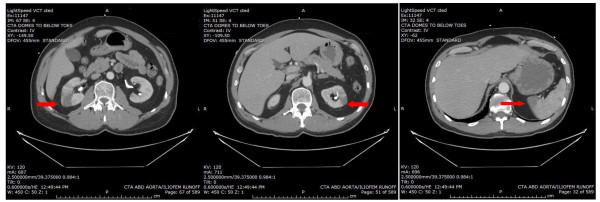

Extension of primary lung tumors into the left atrium via pulmonary veins is a well-documented phenomenon. Peripheral arterial embolism and cerebral embolism originating from a primary lung neoplasm are rare events. We report a case of simultaneous acute bilateral lower limb ischemia, bilateral renal infarction, splenic infarction and cerebral infarction as a result of multiple emboli originating from primary lung malignancy invasion of the left atrium. An emergent embolectomy revealed pathologic features of the extracted thrombus that were identical to the pulmonary neoplasm.

原发性肺肿瘤经肺静脉延伸至左心房是一种有充分文献记载的现象。源自原发性肺肿瘤的外周动脉栓塞和脑栓塞是罕见事件。我们报告一例因原发性肺恶性肿瘤侵犯左心房导致多发栓子形成,进而出现同时性急性双侧下肢缺血、双侧肾梗死、脾梗死和脑梗死的病例。急诊栓子切除术显示取出的血栓病理特征与肺肿瘤相同。